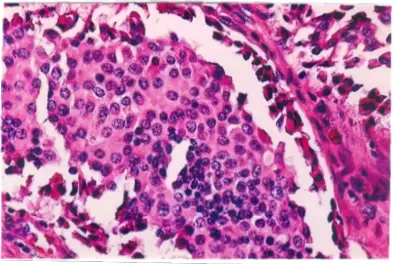

一位 20歲的女大學生最近幾個月來早晨有嗜睡的情形,一直到吃完早餐才會恢復正常。醫師為她做了一系列的檢查,發現在胰臟的尾部長了一個 1公分大小的腫瘤,顯微鏡下的圖形如下圖。則下列那一個診斷最有可能?

胰臟神經內分泌腫瘤(pancreatic neuroendocrine tumor, PNET)中最常見的功能性腫瘤是胰島素瘤(insulinoma),其分泌過量胰島素導致低血糖(hypoglycemia)。本題從臨床症狀(空腹/晨間嗜睡、進食後改善)結合影像和組織病理,考驗對 insulinoma 的識別能力。

顯微鏡下圖片(H&E 染色,高倍)顯示:

- 細胞形態:腫瘤由密集排列的小至中等大小單形性(monomorphic)細胞組成,細胞核呈圓形至卵圓形,染色質呈粗顆粒狀(salt-and-pepper chromatin),此為神經內分泌腫瘤的典型核型特徵。

- 細胞質:豐富的嗜伊紅性或雙嗜性(amphophilic)顆粒狀細胞質。

- 排列方式:細胞呈巢狀(nested)或小梁狀(trabecular)排列,周圍可見纖細的纖維血管間質。

- 異型性:核仁不明顯,核分裂象稀少,符合 WHO G1 低惡性度神經內分泌腫瘤的形態。

- 背景:周圍可見少量紅血球,無顯著壞死。

上述組織學形態與胰臟 beta 細胞腫瘤(insulinoma)的典型病理表現完全一致,有別於腺癌(腺管形成 + 明顯核異型)及其他病變。